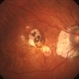

- Myopic Degeneration

- Patient in for follow up for glaucoma. VA is 20/30 in both eyes. Fundus photography shows the RPE loss due to myopic degeneration, nasally, inferiority in the left eye.